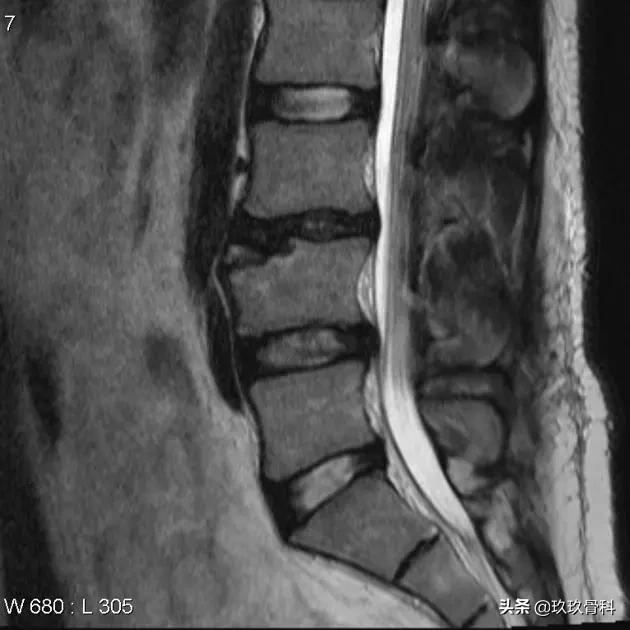

患者伴有长时间的腰背部疼痛史。L4椎体前上缘局灶性骨质缺损,区域内可见一游离的骨性信号。

MRI显示 游离的骨块呈长T1短T2信号,游离骨块与椎体间缺损区与同层椎间盘等信号。